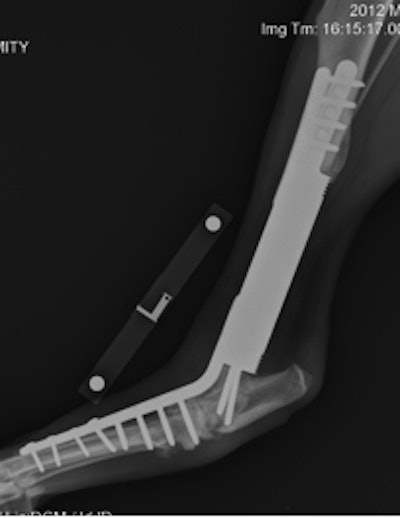

Endoprosthesis collars in a human femur show the same kind of in-growth that are seen in the collars in animals. Image courtesy of Dr. Gordon Blunn, University College London.

"In the tibia or the radius, you can see the bone growing down around the end of the endoprosthesis," he added, showing radiographic images of the hydroxyapatite collar on the end of endoprostheses in the canine tibia, radius, and ulna (see images).

This is relevant because the same operation that is done in man's best friend can be done in man himself and may last for life. He referred to the work of Dr. Gordon Blunn at University College London, with whom Fitzpatrick collaborates. He described a little girl with an osteosarcoma who had it removed and replaced with an artificial knee. "The endoprosthesis grew inside her leg," Fitzpatrick said. "She places her leg inside an electromagnetic field and it grows as she grows. This was pioneered in animals and fortunately humans benefit too. Again, everybody wins."